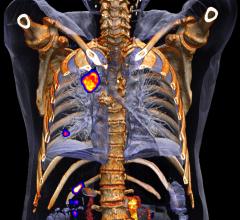

In metastatic breast cancer, prognosis and treatment is largely influenced by estrogen receptor (ER) expression of the metastases. However, little is known about ER expression across metastases throughout the body and surrounding normal tissue. Using a positron emission tomography (PET) tracer, researchers in the Netherlands have been able to identify differences in ER expression, which could help guide treatment for metastatic breast cancer patients. The study is featured in The Journal of Nuclear Medicine’s August issue.